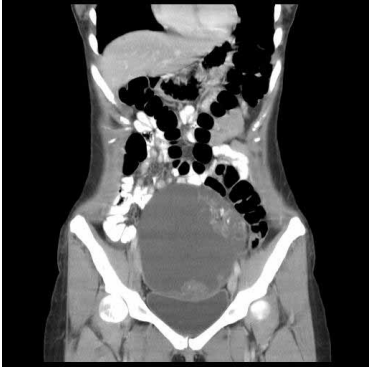

73 一位 25 歲女性,主訴下腹部疼痛,腹部 CT 影像如附圖,最可能的診斷為下列何者?

(A)子宮內膜癌 (B)子宮頸癌 (C)子宮肌瘤 (D)畸胎瘤